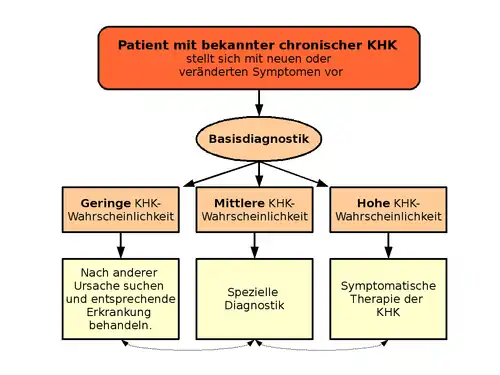

Untersuchungsmethoden

An erster Stelle steht die Basisdiagnostik. Die Diagnosemaßnahmen, die ein Arzt einleitet, um eine chronische KHK zu diagnostizieren, hängen ab von der Manifestation der KHK und dem Schweregrad. Der typische an chronischer KHK erkrankte Patient leidet meist unter einer stabilen Angina pectoris. Bei diesen kann mit Hilfe einer ausführlichen Anamnese mit Risikostratifizierung, einer körperlichen Untersuchung, der Auswertung verschiedener Laborparameter sowie der Interpretation eines Ruhe- und Belastungs-Elektrokardiogramms eine relativ sichere Verdachtsdiagnose erhoben werden. Eine erweiterte Diagnoseprozedur ist meist nicht erforderlich.

Dagegen ist die Diagnose einer asymptomatischen KHK schwierig. Die Erstmanifestation der KHK ist in diesen Fällen sehr häufig das akute Koronarsyndrom. Allerdings können regelmäßige Hausarztbesuche mit auf den Patienten zugeschnittenen Untersuchungen dazu beitragen, dass diese Form rechtzeitig erkannt wird, bevor es zu einer lebensbedrohlichen Komplikation kommt. Bei Patienten mit Verdacht auf ein akutes Koronarsyndrom unterscheidet sich die Diagnoseprozedur maßgeblich zur chronischen KHK.

Bei Verdacht auf eine obstruktive KHK empfiehlt die europäische Leitlinie (Stand 2019) eine CT-Angiografie oder einen nichtinvasiven Ischämie-Test, gegebenenfalls gefolgt von einer invasiven Koronarangiografie.[18]